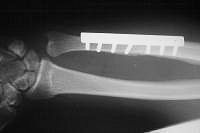

Late result: proper ulnar alignment restored.

The osteotomy and plate position are planned using a seven hole plate with a compression screw positioned obliquely across the osteotomy cut.